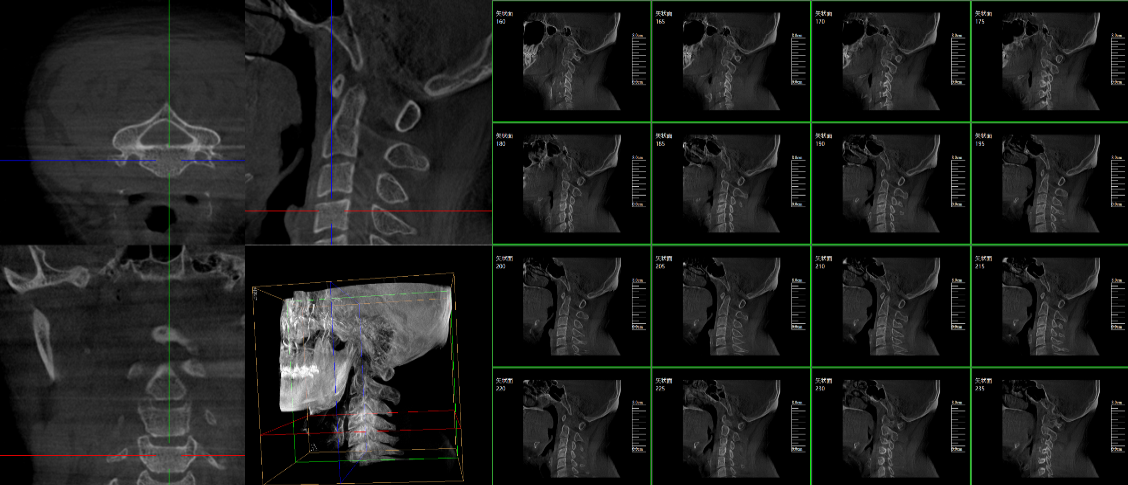

三維C臂,作為“術(shù)中CT”,能在術(shù)中快速地生成橫斷面、矢狀面、冠狀面和可旋轉(zhuǎn)的立體圖像,給術(shù)者提供360°無死角的觀察角度,全方位準(zhǔn)確判斷骨組織和植入物的情況,為手術(shù)的實(shí)施提供保障,極大提高手術(shù)成功率,減少并發(fā)癥概率。主要適用于骨科、脊柱外科、矯形外科、創(chuàng)傷骨科及手術(shù)室等。

普愛醫(yī)療三維C形臂具備術(shù)中實(shí)時(shí)三維成像,術(shù)中三維成像和橫斷面圖像提供多角度的手術(shù)診斷信息,輔助醫(yī)生進(jìn)行術(shù)中評估判斷,諸如骨折復(fù)位情況和內(nèi)植入螺釘?shù)某叽绾臀恢?,輔助手術(shù)更好地完成;三維成像視野大,提供更大的術(shù)中三維成像視野,采集更多圖像信息,可一次拍全全段頸椎、全段腰椎、七節(jié)胸椎、雙側(cè)骶骼關(guān)節(jié)、股骨頭及單側(cè)盆骨等。如果您想了解更多普愛三維C形臂優(yōu)點(diǎn)及技術(shù)參數(shù),歡迎咨詢我們。